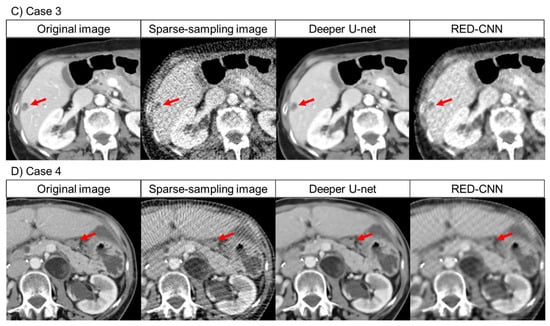

For normal local lesions and abnormal lesions, representative images of the original CT and denoised CT obtained using deeper U-net and RED-CNN are shown in Figure 2. Additionally, representative images of the original CT, the sparse-sampled CT images before denoised processing and denoised CT obtained using deeper U-net and RED-CNN are shown in Figure 3.

Figure 2.

Representative images of the original CT and denoised CT obtained using deeper U-net and RED-CNN. Note: (A) Visual scores of common iliac artery (red arrow): 5 points for deeper U-net, 2 points for RED-CNN for reader 1; 4 points for deeper U-net, 2 points for RED-CNN for reader 2. (B) Visual scores of liver metastasis (yellow arrow): 3 points for deeper U-net, 2 points for RED-CNN for reader 1; 4 points for deeper U-net, 2 points for RED-CNN for reader 2. Abbreviation: RED-CNN, Residual Encoder-Decoder Convolutional Neural Network.